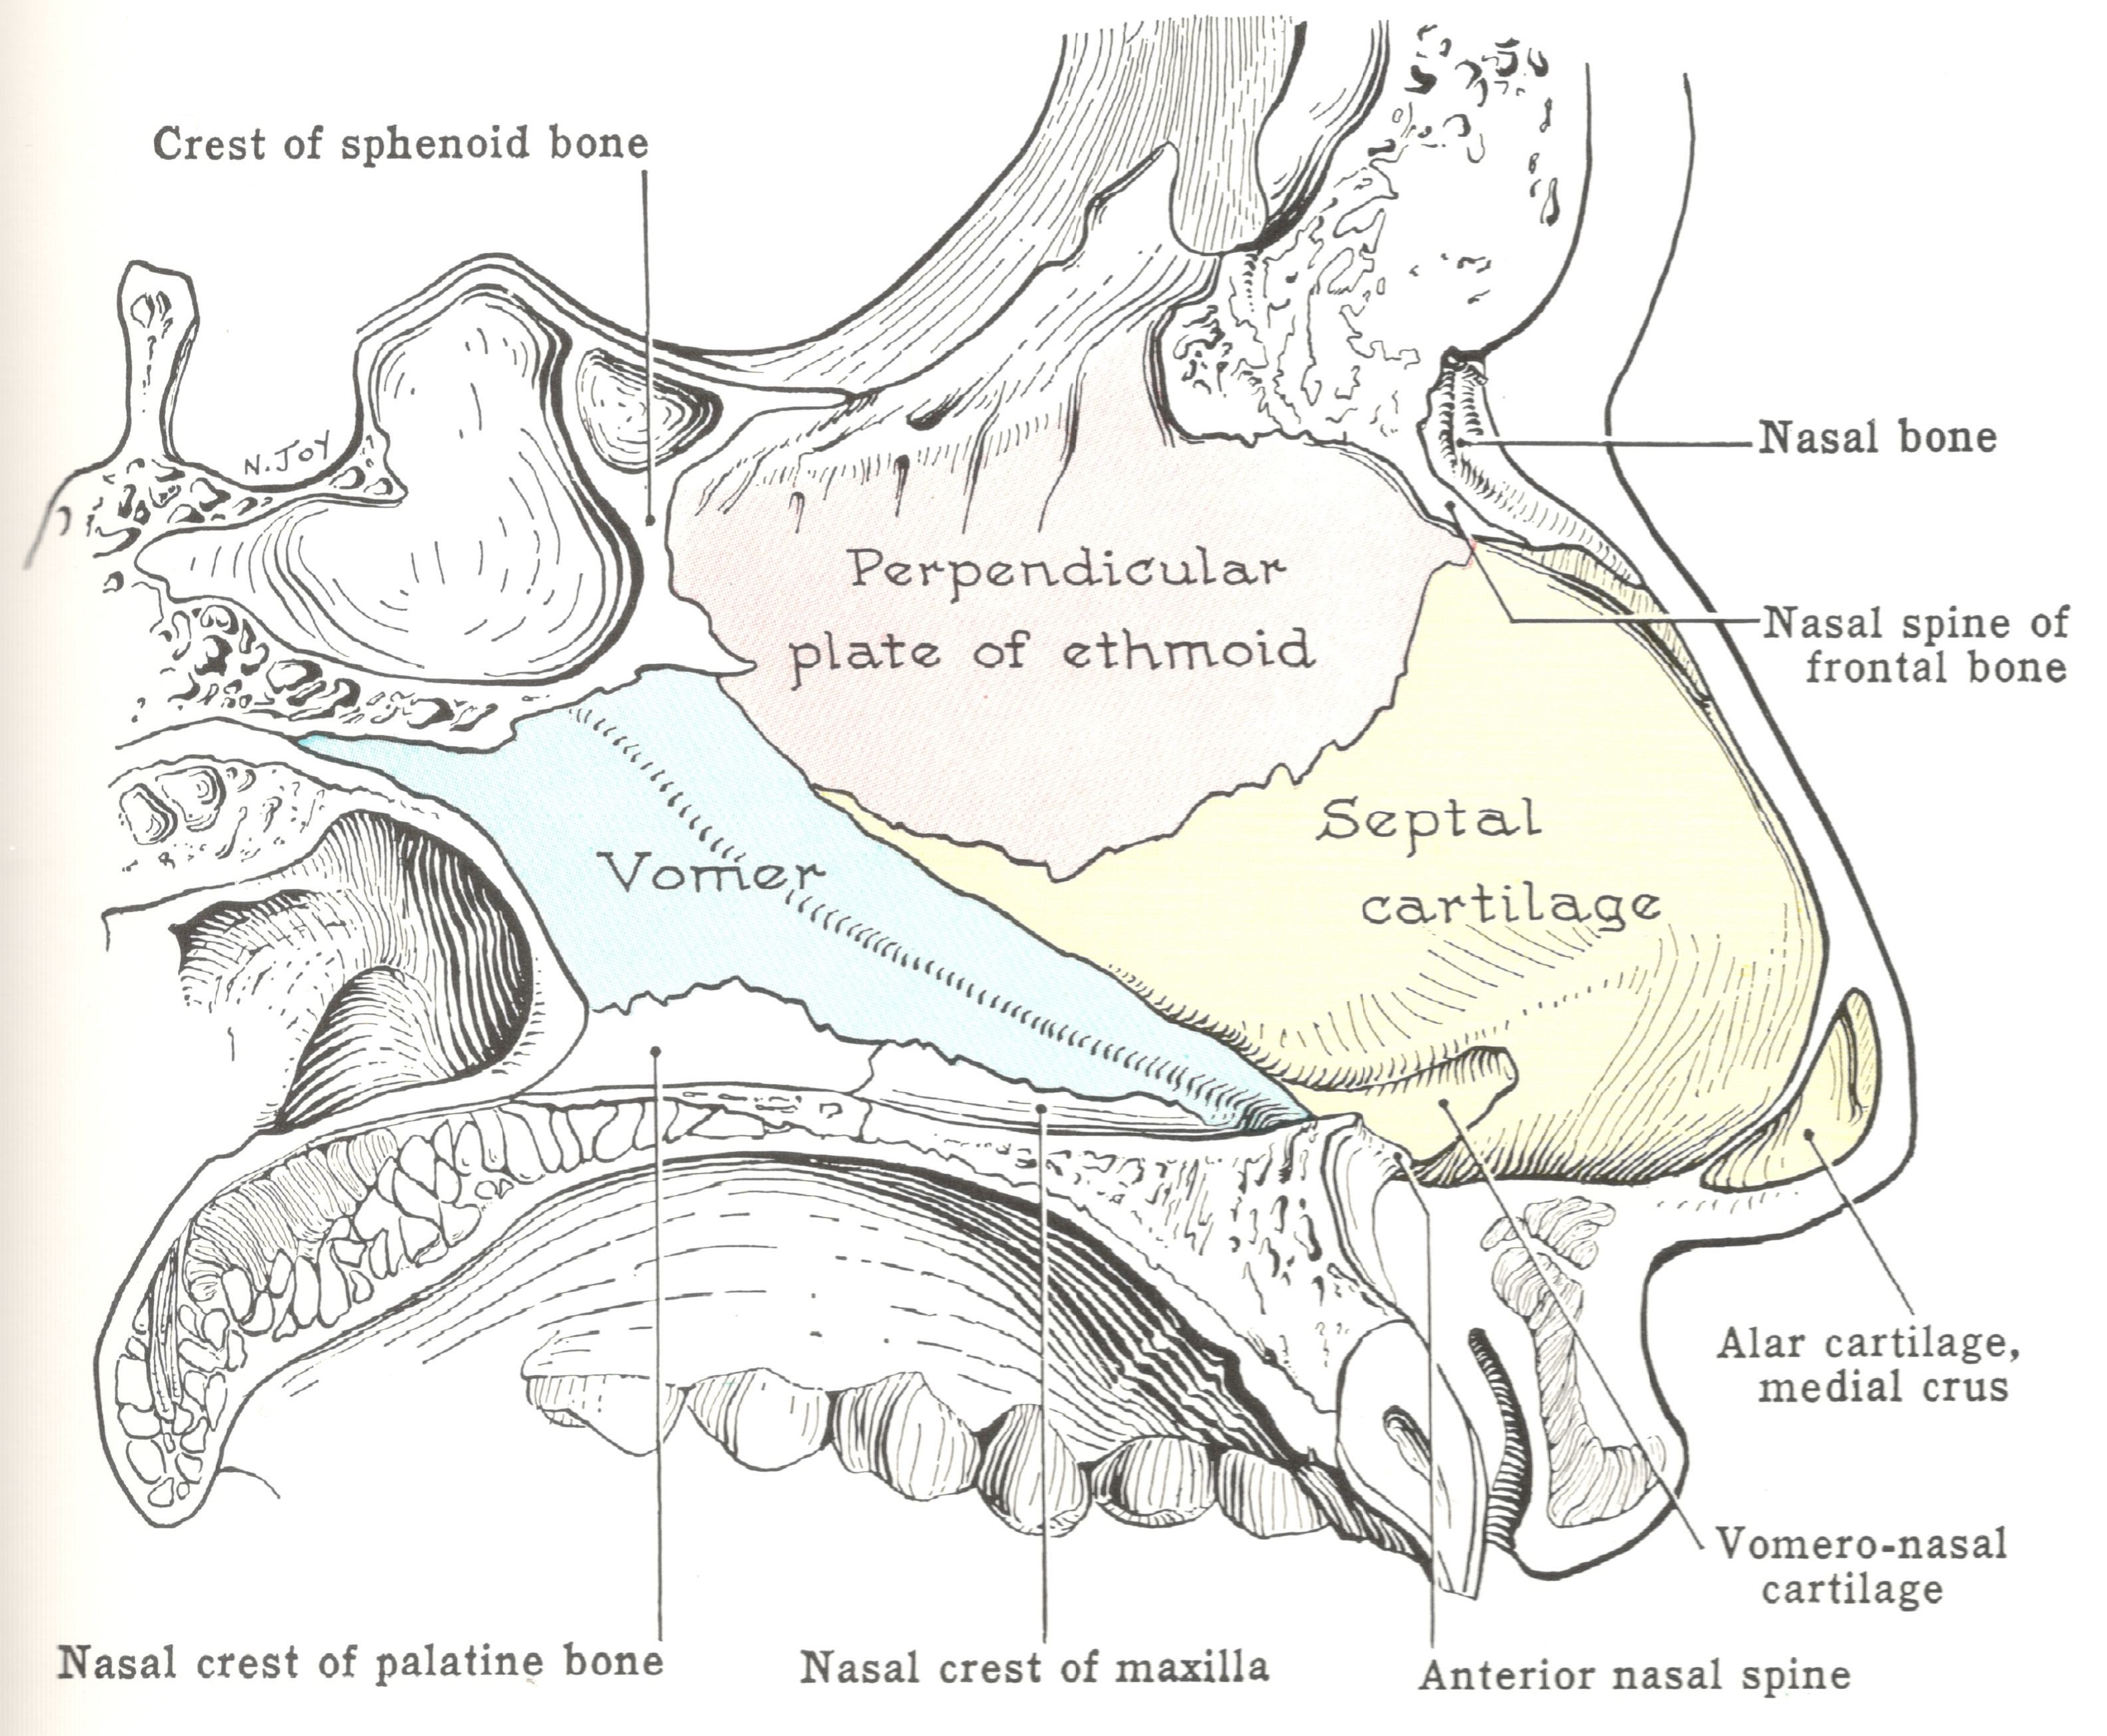

Nose

Bone

- Frontal (nasal process)

- Maxilla (frontal process)

- Nasal

Cartilage

- Septal

- Lateral nasal

- Alar

Nasal septum (鼻中膈)

- nasal sepal cartilage

- perpendicular plate of ethmoid

- vomer